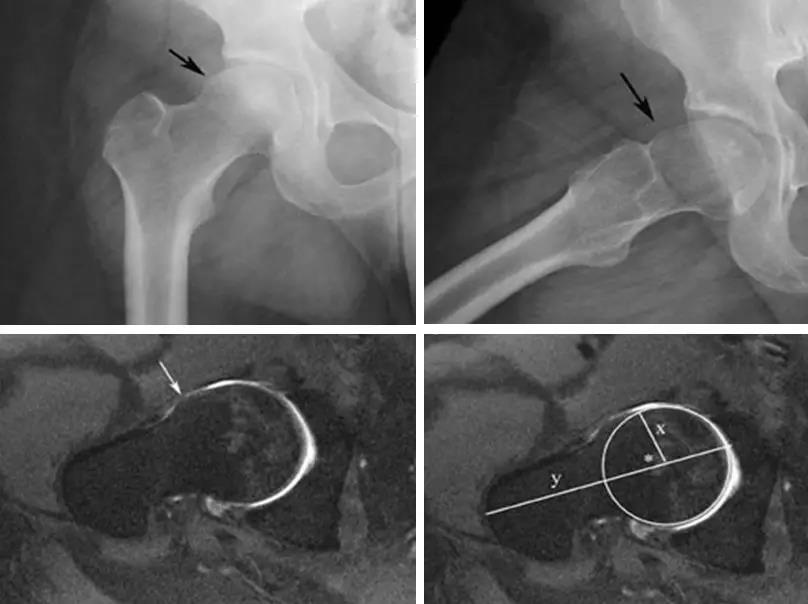

凸轮撞击型FAI▼

- 股骨头颈间的凹陷不足,伴局部的骨质增生。

- 股骨头颈的“ 枪柄样” 畸形。

- 偏心距是水平位投照平片上平行的股骨颈切线与股骨头前缘之间的距离。

- 正常值为11.6mm。

- FAI偏心距缩短<7.2mm。

- 股骨头中心O点为圆心,股骨头正常最大半径为r,从股骨头颈连接处骨质与这个圆的交点(A点)到股骨头中心点作直线OA,此直线与股骨颈中轴线OB的交角为α角。

- 反映股骨颈骨赘突出程度,α角越大,越容易发生前上方股骨头颈与髋臼唇的撞击。

- FAI组中该角平均为74.0°±5.4°,正常对照组为42.0°±2.2°。

- α角>50°是诊断FAI的临界值。

- 股骨头颈联合处前上缘骨性突起。

- 非圆形的股骨头。

- 股骨头颈联合处前缘骨性突起、骨质硬化,α角增大。

- 凸轮撞击型FAI--并盂唇撕裂。